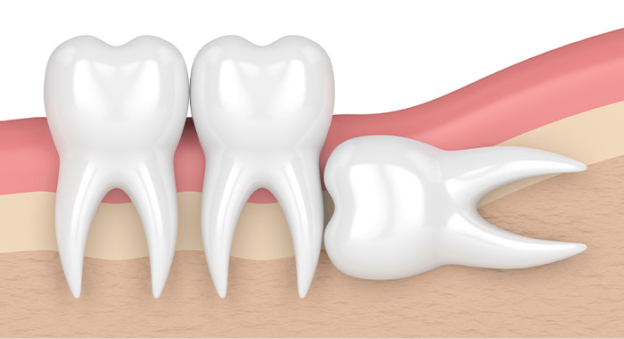

삐뚤어져 나는 사랑니

사랑니가 삐뚤게 자라면 주변 치아의 뿌리를 녹이거나 인접한 면에 음식물이 잘 끼게 되어 충치가 생길 수 있습니다.

옆으로 누워서 자란 사랑니

사랑니가 누워서 자라면 바로 앞쪽 어금니 뿌리를 압박해 염증 등의 문제를 일으키거나 앞쪽 어금니와의 사이에 음식물이 잘 끼게 되어 충치와 염증을 유발할 수 있습니다.